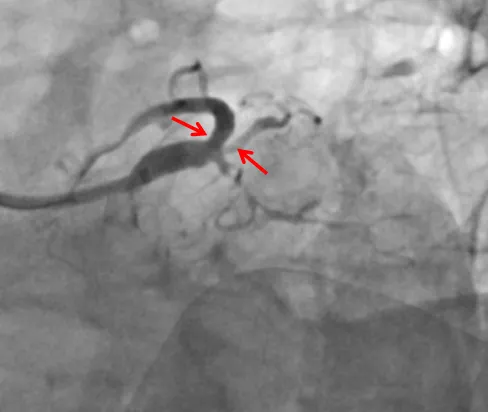

▲右冠脉多发弥漫严重狭窄,缺血风险高

然而最近一个月,张先生的胸闷症状发作越加频繁,发作时间甚至更长。在家人的陪同下,他前往医院进行检查,冠脉造影检查提示:左主干+多支血管病变,且冠脉病变弥漫、狭窄严重,主干分叉多,左边的前降支、回旋支和中间值仅遗留一丝丝血流供血,右冠脉全程弥漫性狭窄,远端也重度狭窄90%,诊断冠心病明确,且冠脉病变高危复杂,可以说是“心悬一线”。